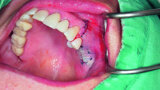

Fig. 18: Placement of two GC Aadva Standard implants with regard to the future restorative margins.

Fig. 19: Bone defect filled with xenograft and covered with an absorbable collagenous membrane.